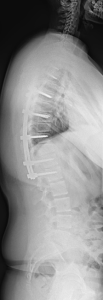

Skoliose

Unter Skoliose versteht man eine dauerhafte Seitverbiegung und Rotation der Wirbelsäule mit gleichzeitiger Verdrehung der Wirbelkörper. Nach ihrer Herkunft lassen sich verschiedene Formen unterscheiden (idiopathisch, kongenital, neuromuskulär, adult), die sich hinsichtlich des Erkrankungsalters, der Ausprägung, des Fortschreitens der Erkrankung und der möglichen Behandlungsverfahren unterscheiden.